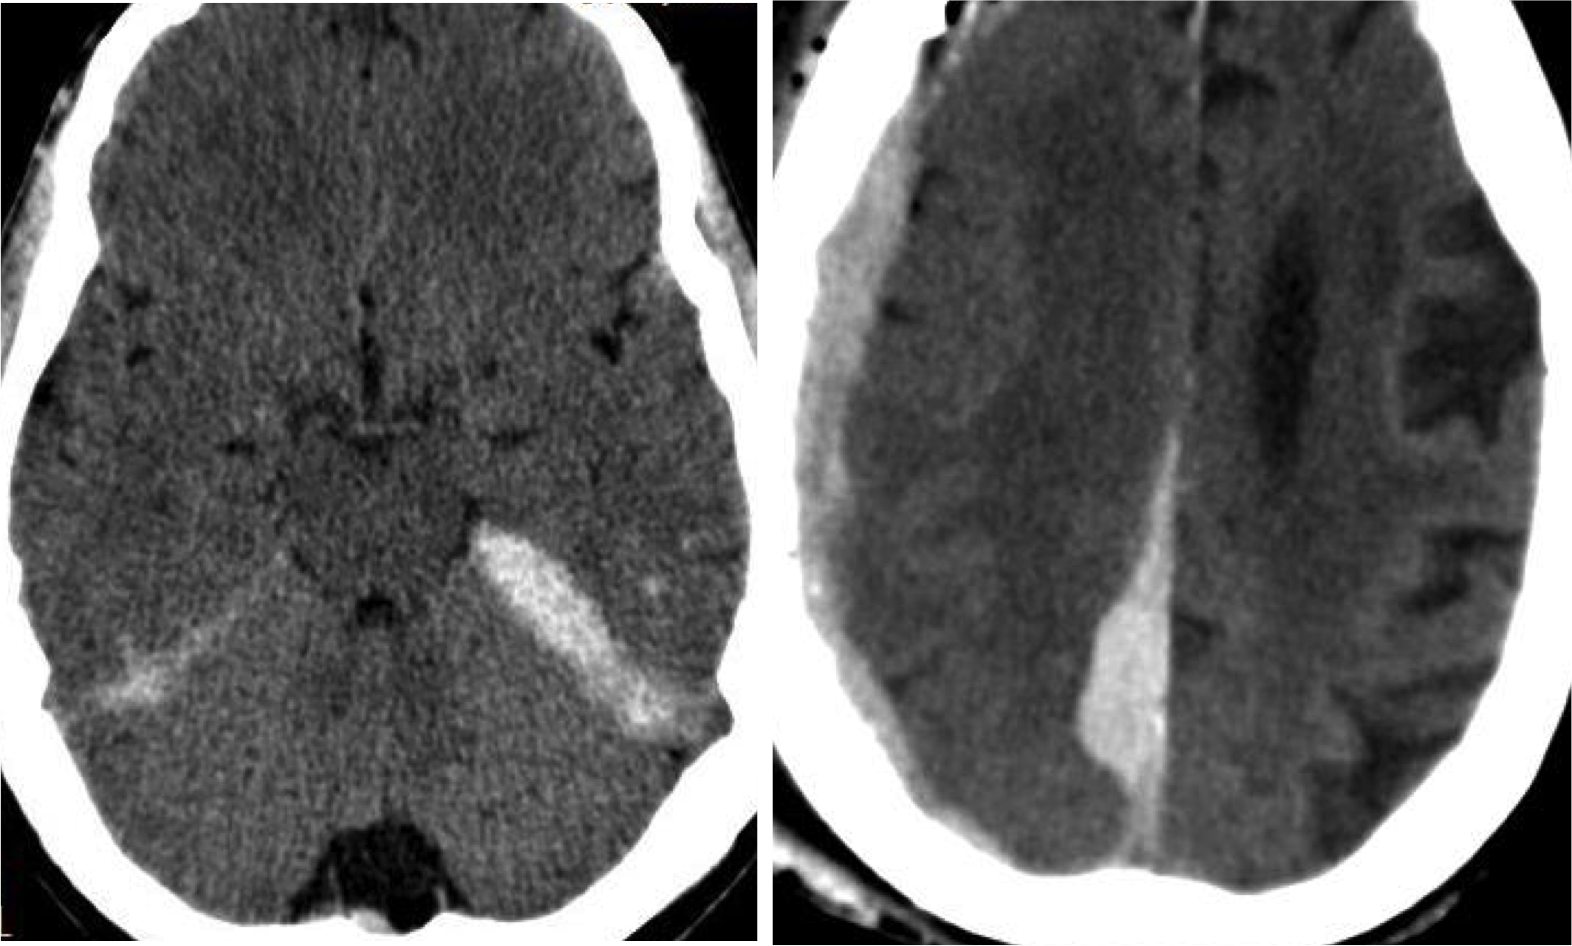

Contusiones.

- Son las lesiones más frecuentes tras un traumatismo, especialmente en personas mayores.

- Son la expresión de laceraciones del parénquima cerebral tras un golpe o contragolpe, dónde suelen ser de mayor tamaño.

- Focos hiperdensos uni o multifocales parcheados y mal definidos. De localización cortical (trauma leve) y/o subcortical (trauma más severo).

- Lóbulo frontal y temporal son localizaciones más frecuentes debido a que el cerebro se desliza sobre la superficie irregular de la fosa craneal anterior y media.

Nota: La contusión y el hematoma constituye el mismo espectro de daños. Las contusiones hemorrágicas se definen como pequeñas hiperdensidades que afecta preferentemente el córtex con o sin edema periférico con relativa normalidad de la sustancia blanca subyacente en el trauma leve. Pueden incrementar en tamaño con el tiempo, lo que se conoce como progresión hemorrágica.